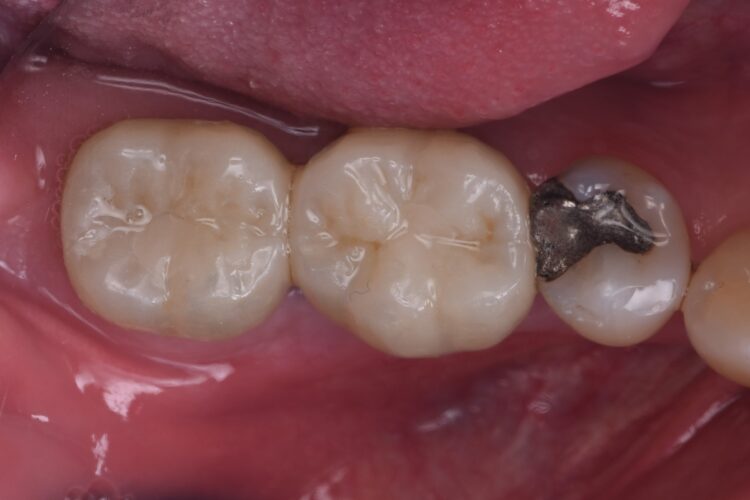

The implant crowns were constructed using custom-milled titanium abutments with a zirconia crown. Care was taken to ensure that any zirconia in contact with the tissues was polished rather than glazed to promote optimal soft tissue health. As seen in the post-treatment photos and x-rays, the hard and soft tissues have been well maintained, with excellent soft tissue thickness and a stable band of keratinised tissue achieved.

The immediate placement of the CONELOG® Progressive-Line implants in both molar sockets proceeded smoothly, achieving excellent primary stability. This approach not only preserved the existing bone and soft tissue but also provided a solid foundation for future prosthetic restoration. The use of MinerOss® Putty (allograft) played a crucial role in maintaining bone volume and soft tissue integrity, further contributing to the long-term success of the implants.

Immediate placement, when feasible, offers significant advantages in simplifying long-term maintenance compared to extensive hard and soft tissue reconstruction. The CONELOG® Progressive-Line implant system continues to be a reliable choice, particularly in molar sites, due to its excellent design and adaptability.